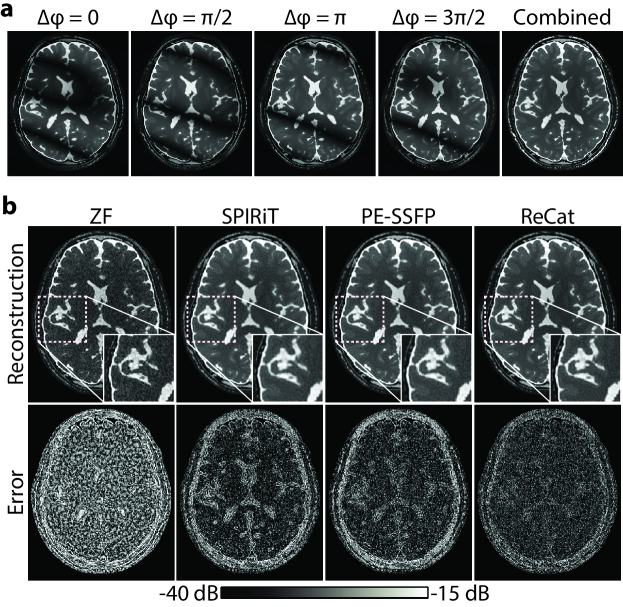

ReCat was first demonstrated on bSSFP acquisitions of a numerical brain phantom with D=8. ZF, SPIRiT, PE-SSFP and ReCat reconstructions and error maps are shown in Fig. 3. Error maps for varying acceleration factors R={4,8,12}4812\{4,8,12\} are shown in Fig. 4. SPIRiT that independently processes separate acquisitions and PE-SSFP that independently processes separate coils suffer from broad errors at high-spatial frequencies. In comparison, ReCat achieves visibly reduced reconstruction error and enhanced tissue depiction, particularly for R>\textgreater4.

Figure 3: Phase-cycled bSSFP acquisitions of a brain phantom were simulated for N=4. (a) Phase-cycle images and the p-norm combined reference image are shown. (b) Representative reconstructions at D=8, R=8 are shown for ZF, SPIRiT, PE-SSFP and ReCat (top row). Zoomed-in portions of the images are depicted in small display windows. ReCat depicts detailed tissue structure with greater acuity compared to other methods. Error maps relative to fully-sampled acquisitions are displayed in logarithmic scale (bottom row; see colorbar). ReCat visibly reduces reconstruction errors compared to alternative methods. For this cross-section, ReCat achieves 30.6 dB PSNR, whereas SPIRiT and PE-SSFP yield 29.6 dB and 29.4 dB, respectively.

Figure 4: SPIRiT, PE-SSFP and ReCat reconstructions of the simulated brain phantom were performed at N=4 and D=8. Error maps are shown for R=4, 8 and 12. ReCat outperforms SPIRiT and PE-SSFP for R>\textgreater4, and the level of error reduction increases towards higher R.